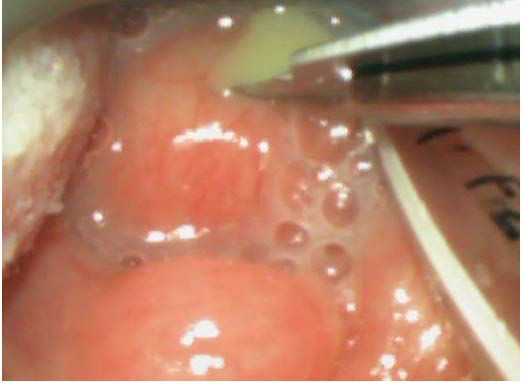

Figure 3: Intraoperative videolaryngoscopy showing pus evacuation after incision.

figure 3